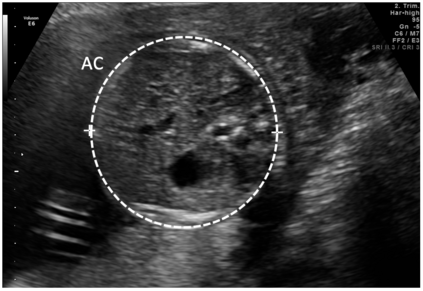

Deep-learning (DL) algorithms are becoming the standard for processing ultrasound (US) fetal images. Despite a large number of survey papers already present in this field, most of them are focusing on a broader area of medical-image analysis or not covering all fetal US DL applications. This paper surveys the most recent work in the field, with a total of 145 research papers published after 2017. Each paper is analyzed and commented on from both the methodology and application perspective. We categorized the papers in (i) fetal standard-plane detection, (ii) anatomical-structure analysis, and (iii) biometry parameter estimation. For each category, main limitations and open issues are presented. Summary tables are included to facilitate the comparison among the different approaches. Publicly-available datasets and performance metrics commonly used to assess algorithm performance are summarized, too. This paper ends with a critical summary of the current state of the art on DL algorithms for fetal US image analysis and a discussion on current challenges that have to be tackled by researchers working in the field to translate the research methodology into the actual clinical practice.